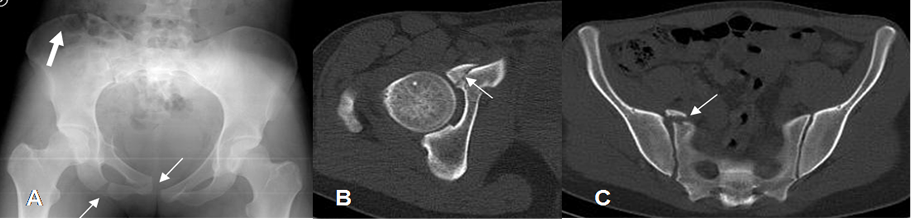

Fig 39. Trauma de pelvis. Compresión lateral.

A: Rx AP. Fractura del ramo isquiopúbico derecho y diastasis de la sínfisis púbica (Flechas delgadas). Adicionalmente hay fractura en el borde superior del iliaco derecho. (Flecha gruesa).

B y C: TAC axial. Además se identifican fracturas del borde medial del acetábulo y la parte anterior del sacro.